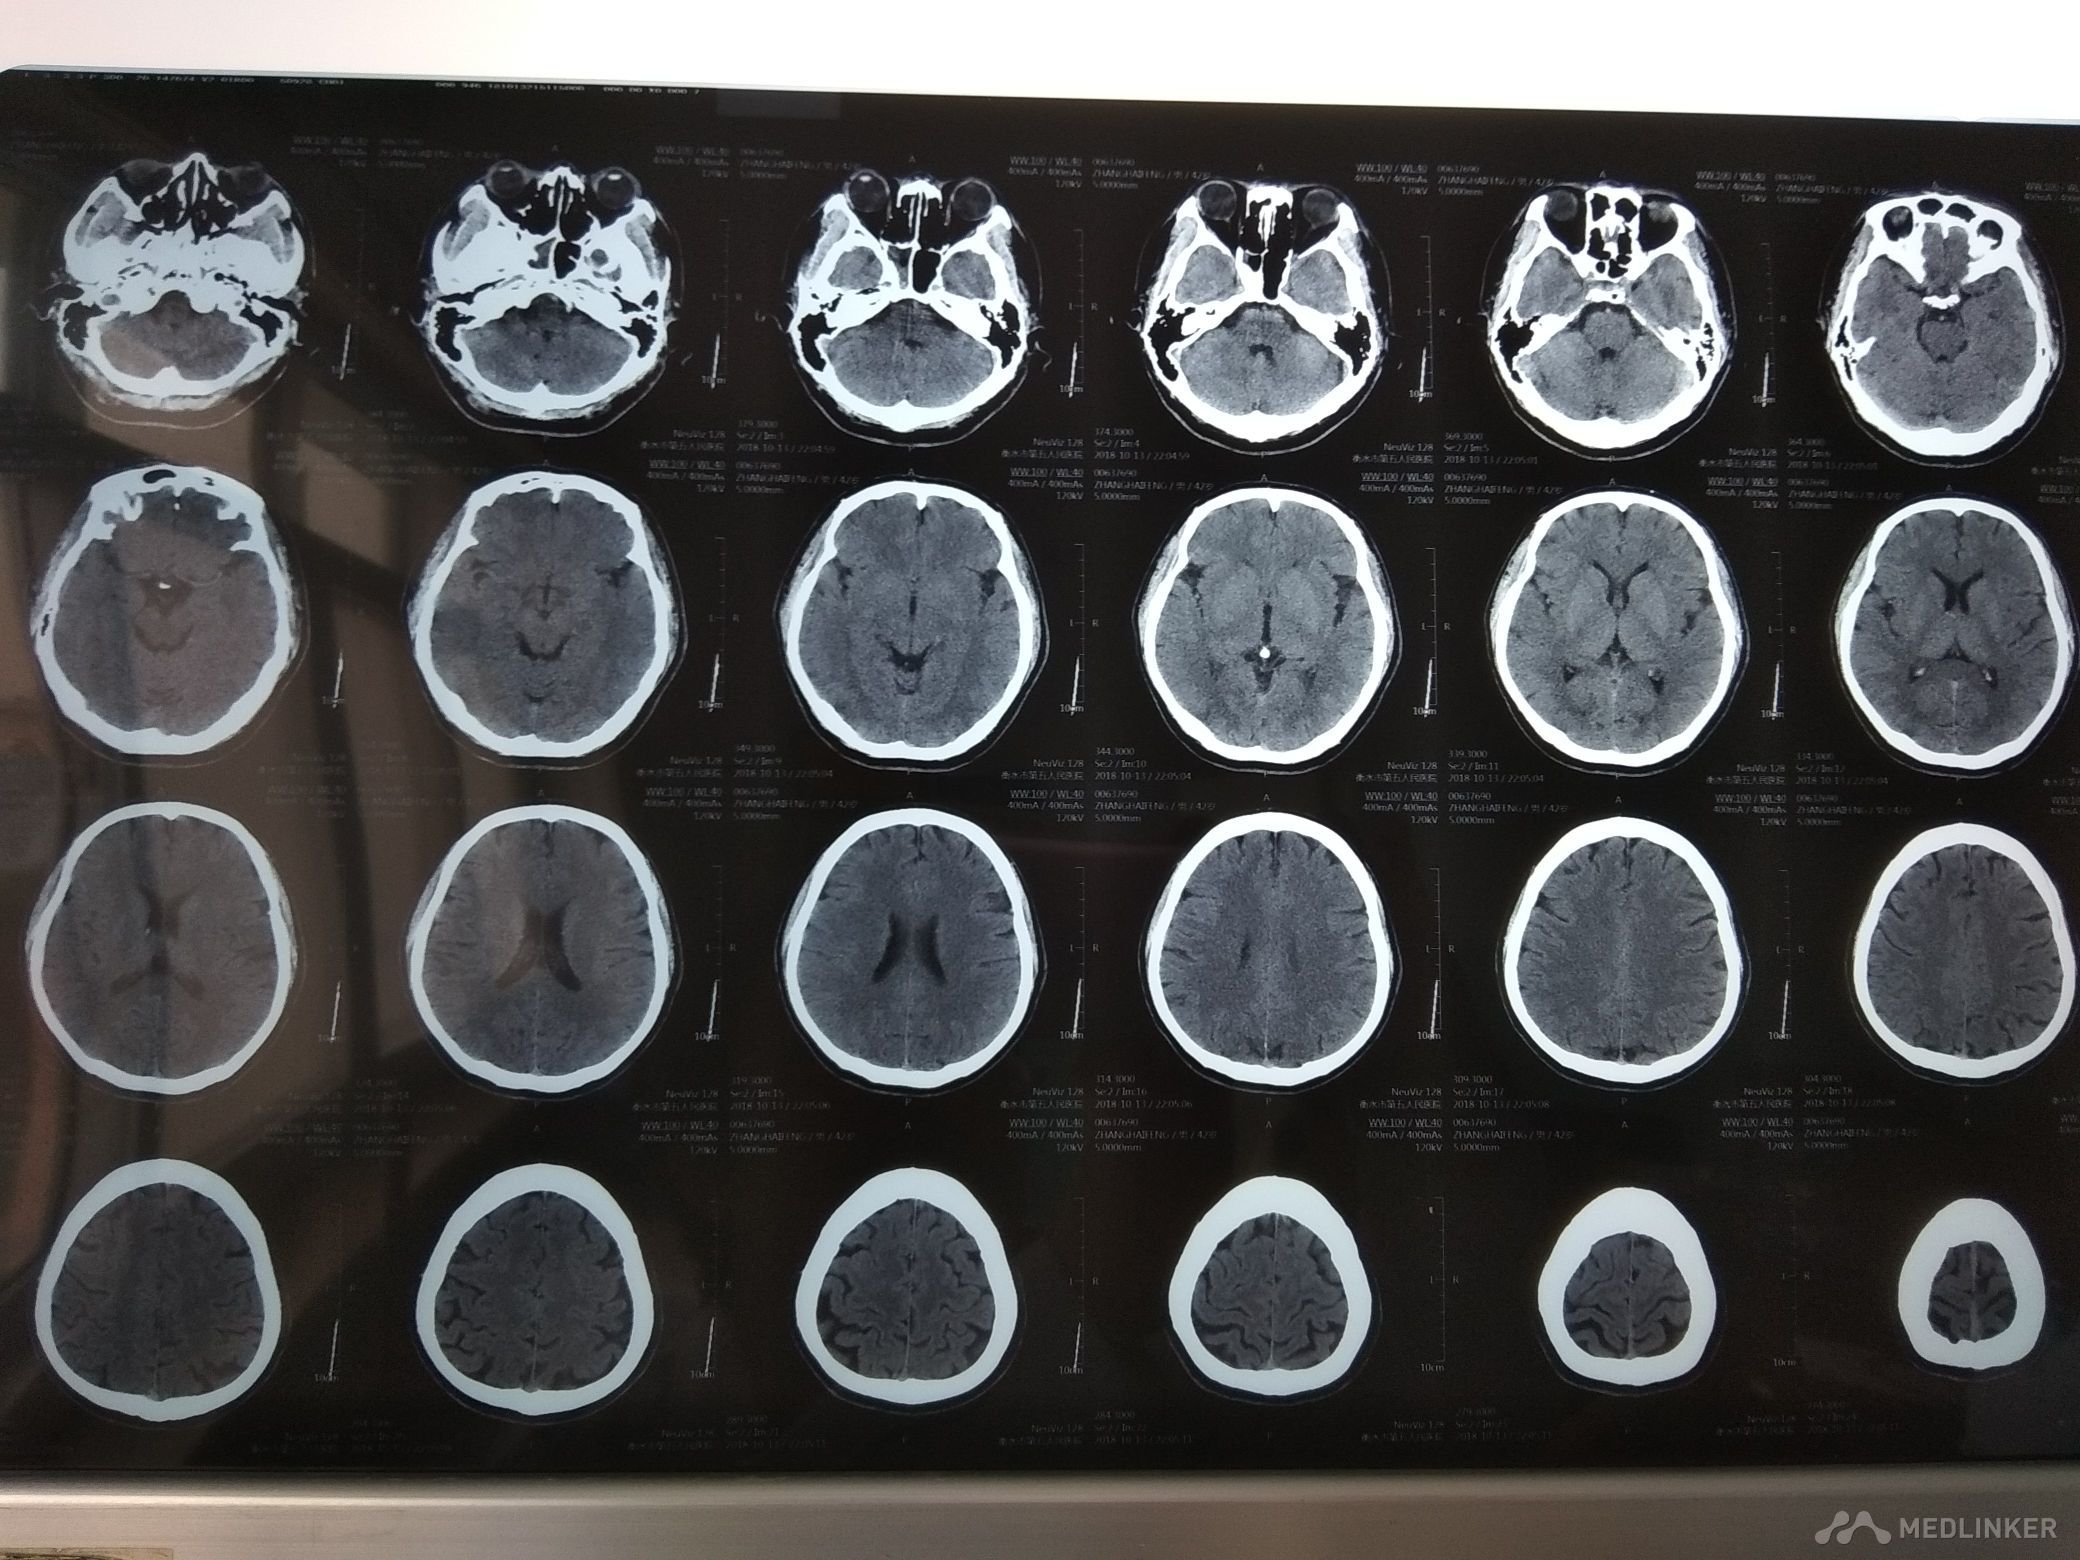

发作性左侧肢体发麻无力1天余。病史 54岁男性患者,于入院前1天无明显诱因出现左侧肢体发麻无力,左下肢明显,不能抬腿走路,左上肢持物不稳。未予治疗,约5分钟缓解。无头晕头痛,无恶心呕吐,无肢体抽搐,无意识障碍,无尿便障碍。共发作3次,为求诊治,遂来我院,以“短暂性脑缺血发作”收入我科。 既往高血压病史,最高180/100mmHg,平时未监测血压。血糖偏高史,未诊治。吸烟饮酒史。

查体BP170/90mmHg,神清,语利,右利手,计算力,记忆力,定向力,理解判断力正常。鼻唇沟基本对称,伸舌居中

,四肢肌力5级,肌张力,腱反射适中对称,针刺觉两侧对称,共济检查较稳准,双侧病理征未引出。颈软,双下肢无水肿。肺心腹未见明显异常。 心电图大致正常, 化验结果:血常规,血凝,电解质,肝肾功能,心肌酶,血脂,血糖,甲功七项,同型半胱氨酸正常。

诊断 短暂性脑缺血发作,高血压3级 很高危。 治疗 予阿司匹林抗血小板聚集,稳定斑块,改善循环,营养神经等治疗。